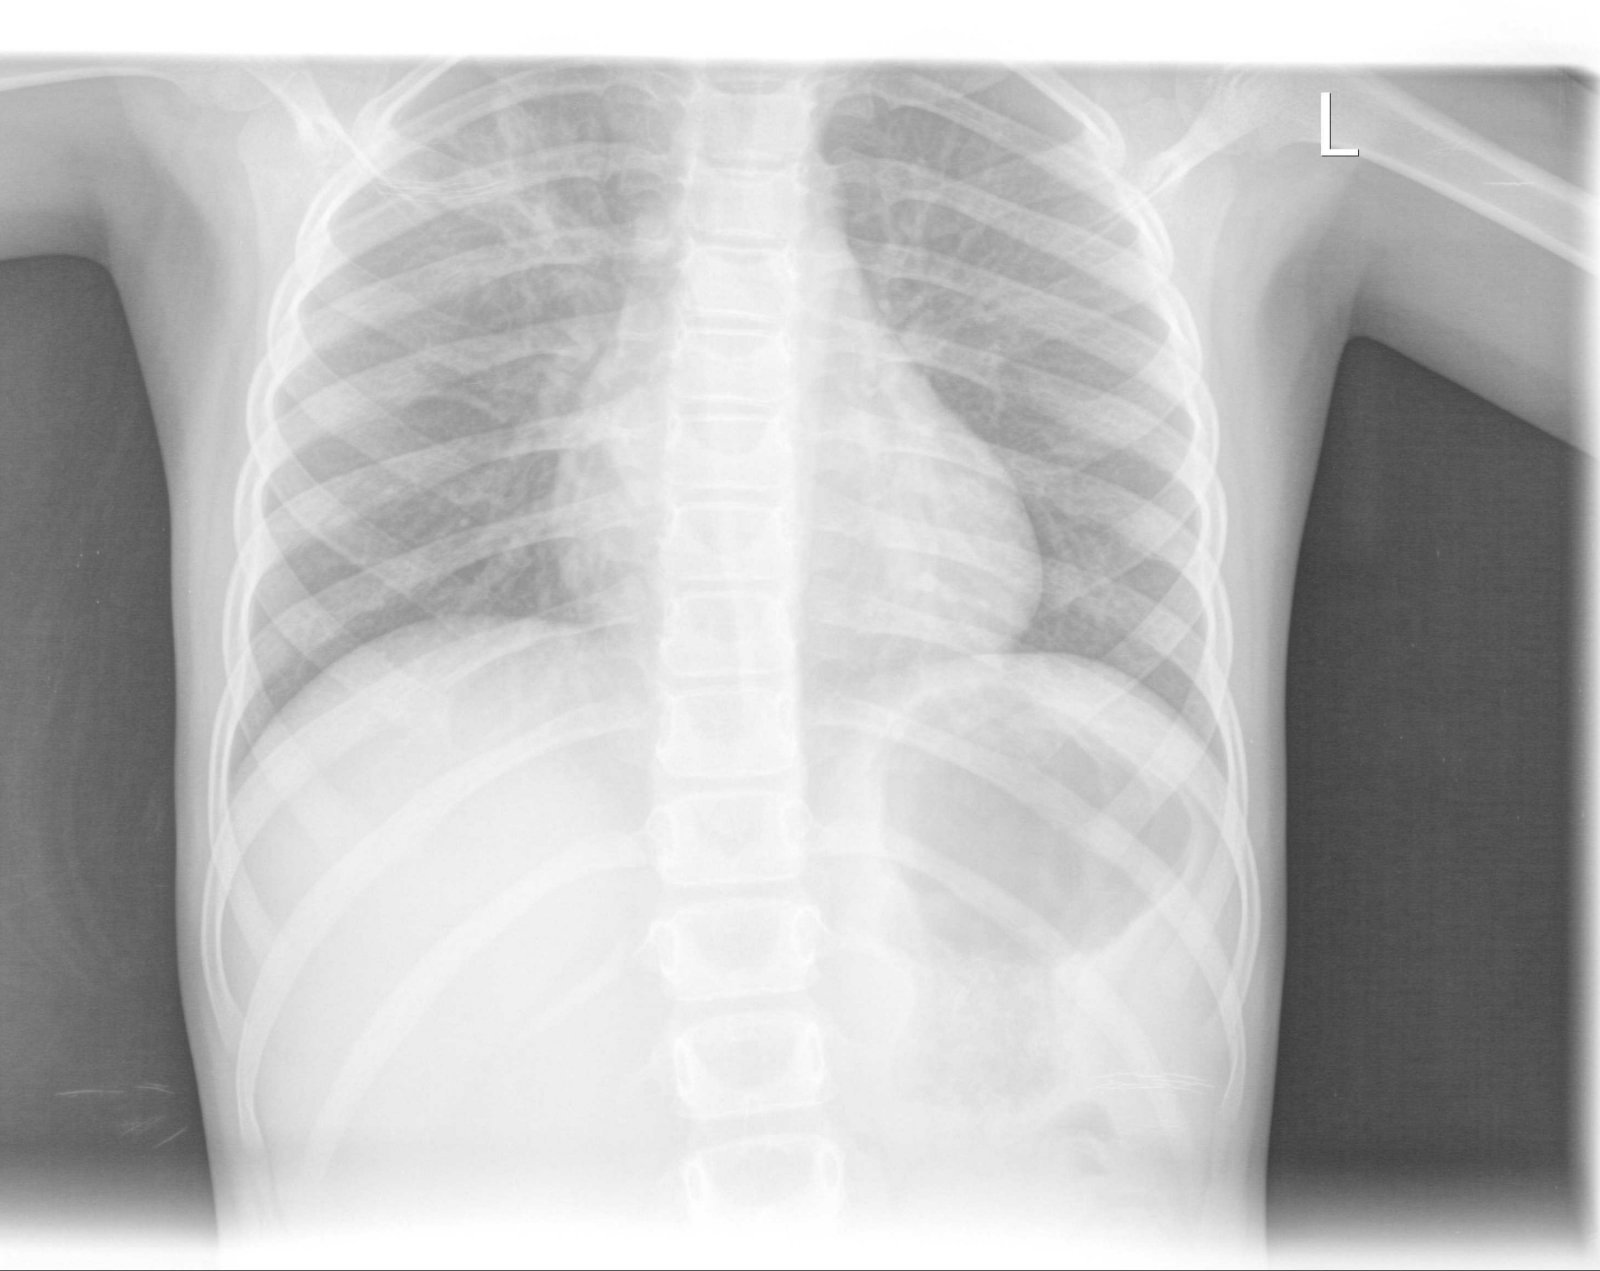

Детето започна с много висока температура около 40 градуса 3-4 дни,които почти не се повлияха от антипиретици и Хексалгин.Също и повръщане.След първият рентген ни назначиха два венозни антибиотика-7 дни-Медаксон и Амикацин ,инхалации с Пулмикорт ,Вентолин ,Урбазон и системи.Интересно беше ,че още след първата венозна апликация температурите изчезнаха.В болницата непрекъснато ни се натякваше ,че положението е много тежко,вероятно да се оправдае дългото лечение .Кръвните резултати -не бяха много добри.Суе-82 ,при изписването спадна